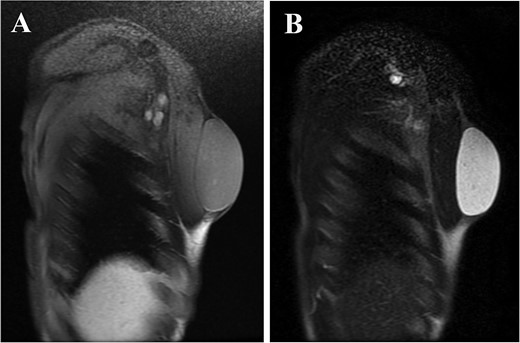

A 61-year-old man presented to the outpatient breast clinic with a painless lump in his right pectoral region. The lump was first noticed 40 years earlier at the size of a small fingertip and gradually increased. The lump was approximately 90 mm in diameter, well-defined, and dome-shaped. The overlying skin appeared glossy with no visible puncta (Fig. 1). Erythema or bruising was not observed. On palpation, the lump was non-tender and doughy with no localized temperature increase. It was not fixed to underlying tissue. On ultrasound imaging, the lump showed a hypoechoic and well-circumscribed oval mass containing variable echogenic foci and filiform anechoic areas without color Doppler signals (Fig. 2). The lump was located in the subcutaneous fat layer, with extensive dermal apposition. In sagittal magnetic resonance imaging (MRI), the lump showed a unilocular and well-defined cystic mass (70 × 40 × 90 mm) (Fig. 3A and B). The cyst content showed an isointense signal relative to the muscle with no enhancement in the sagittal enhanced T1-weighted image (Fig. 3A), and a hyperintense signal in the T2-weighted image (Fig. 3B). Ultrasound-guided percutaneous CNB was performed, and six core specimens containing cystic walls ware sampled (Fig. 4A). The cystic wall was lined with mature stratified squamous epithelium with a granular layer and did not contain an adnexal structure (Fig. 4B). In addition, many laminated or basket-woven keratin layers were sampled. These findings ware consistent with those of an epidermal cyst. The mass was excised under general anesthesia. The mass was well-defined and did not adhere to the surrounding structures, except for a portion of the CNB (Fig. 5). The mass was easily excised. The formalin-fixed mass was covered with a thick white fibrous capsule (Fig. 6A), which was filled with grey substances, such as bean curd residue, in the cross-section (Fig. 6B). After the removal of the contents, the internal surface of the capsule was crepey, and no nodules were observed (Fig. 6C). The definitive pathological diagnosis was an epidermal cyst without any malignancy. The adhesive region revealed keratin, which flowed outside the cyst, and a granulomatous response to keratin with multinucleated giant cells (Fig. 7). No complications or recurrences were observed during the one-year follow-up after surgery.

Six core needle specimens containing cystic walls were sampled by core needle biopsy, hematoxylin, and eosin stain, ×2 magnification (Fig. 4A). Cystic wall was lined by mature stratified squamous epithelium with granular layer and did not contain adnexal structure, hematoxylin, and eosin stain, ×20 magnification (Fig. 4B).